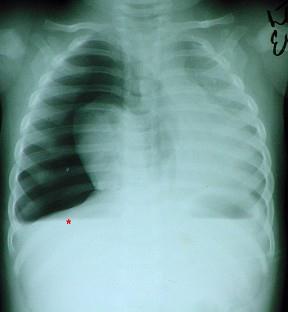

问题 患者,男性,3岁,因车祸伤半小时,急诊来院。患者呼吸极度困难,口唇发绀,烦躁不安。右侧胸部饱满肋间隙增宽,颈部胸部广泛皮下气肿。听诊右侧呼吸者消失,胸片检查如图。最可能的诊断 ( )

选项 A、创伤性窒息 B、肺爆震伤 C、血胸 D、张力性气胸 E、单纯性气胸

答案 D